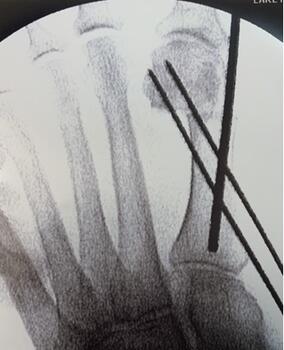

Next, the surgeon should rotate the hallux in a varus position to correct the frontal plane deformity (see fourth photo above). Once the metatarsal head is translated and the frontal plane is reduced, one can hold the reduction with the non-dominant hand. A large K-wire or Steinmann pin should capture the medial capsular tissue at the hallux and metatarsal head. This step can be performed prior to obtaining reduction of the metatarsal head to allow for easier placement into the metatarsal shaft. Following reduction, the surgeon will advance this wire intramedullary to the metatarsal base or across the first TMTJ for additional stability (see fifth photo above). Another method to maintain correction is to provisionally fixate the first metatarsal head to the second with a K-wire, with the intermetatarsal angle and tibial sesamoid position corrected. Consider lateral capsular or fibular sesamoid release if reduction is difficult. Also, consider an MIS Akin if the hallux remains in valgus or when there is an intrinsic deformity to the digit.

Wire Placement For Percutaneous Screw Fixation. Surgeons may place wires in the first metatarsal before the osteotomy, from the medial aspect of the first metatarsal up to the lateral cortex. Following osteotomy of the metatarsal, the surgeon can then shift the metatarsal head and advance the wires to capture the fragment. This will prevent loss of reduction after manipulation. The proximal wire should be just distal to the first tarsometatarsal joint, while the distal wire should be approximately two cm proximal to the osteotomy site. The distal wire does not need to purchase the lateral cortex of the first metatarsal. The proximal wire must purchase the lateral cortex of the first metatarsal and may exit bone before re-entering the metatarsal head. Be cognizant of maximum screw length to help in planning of wire trajectory (see eighth photo above).